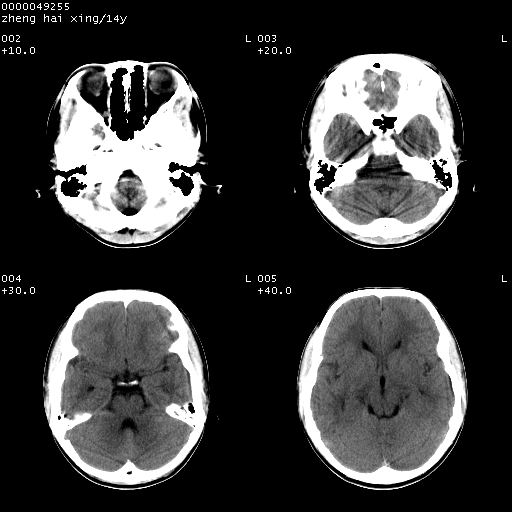

患儿 男,14岁。头部外伤1小时。pe:发育正常,营养良好,生命体征稳定,未见明显阳性体征。

临床诊断:ⅰ级脑外伤。

颅脑ct轴位平扫(层厚、层距均为10mm),图像如下:

(患儿平素健康,双眼视力正常,无神经系统及内分泌系统症状及体征)

双侧侧脑室之间无透明隔,双侧额角前方变扁,交角变钝。支持透明隔缺如!

透明隔缺如可为先天性缺如,亦可继发于因脑积水,脑室内压力增高,使其变薄,以至不能显示。一般无临床意义,但可并发于其他畸形或作为隔—视综合征的组成部分。

(隔—视发育不良综合征包括:1)原发性视神经发育不良,2)透明隔缺如,3)垂体功能不全,特别是生长激素不足或缺乏)